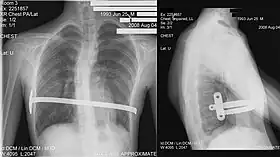

X-Ray of a 15-year-old male after undergoing the procedure | |